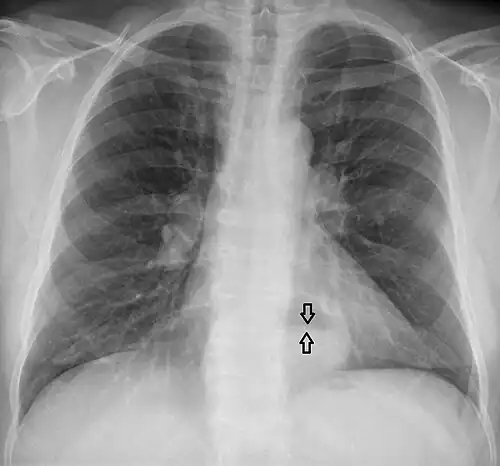

-

A large hiatal hernia on chest X-ray marked by open arrows in contrast to the heart borders marked by closed arrows

This hiatal hernia is mainly identified by an air-fluid level (labeled with arrows). -